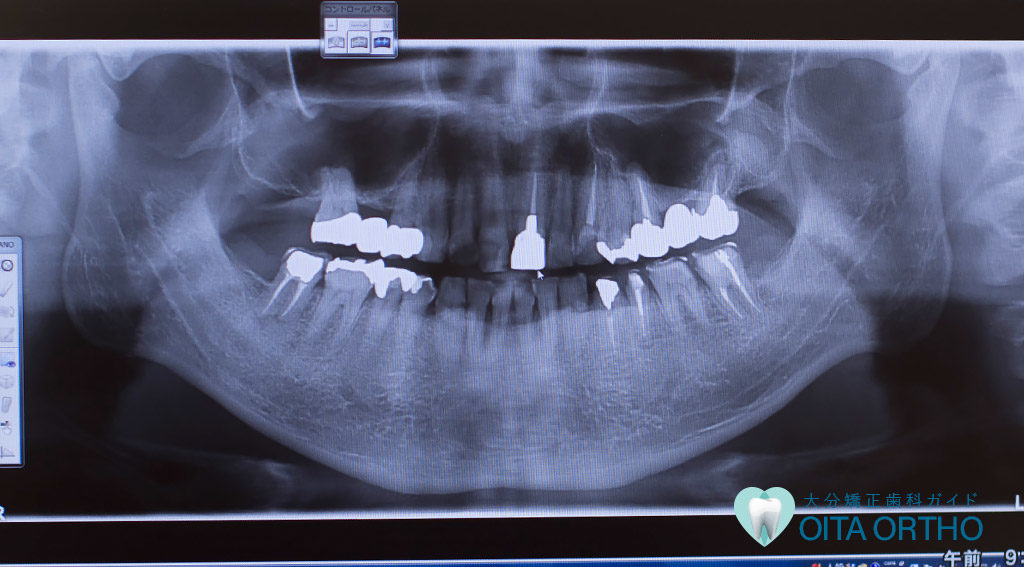

お口の病気とケア インプラント差し歯 差し歯があっても矯正歯科治療が可能か? 2019年7月28日 年齢が高くなるにつれ、さまざまなお口や歯の病気にかかってしまう機会は増えていきます。したがって歯の健康のために、歯の神経を抜き、差し歯などの被せ物をしたり、あるいはブリッジやインプラント、また入れ歯などの対処を余儀なくされた方も多いのではないでしょうか。 そんな中、矯正治療に興味はあるけど、差し歯などをしていても矯正治...

お口の病気とケア 歯科用CT 歯科の診断・治療に使われるX線 2019年7月24日 歯科における「X線」とは、歯科治療の補助として行う、X線を用いた「写真撮影」のことです。 主な対象として、歯、歯茎、顎の骨などがあり、X線写真から得られる情報は歯科治療において不可欠なものです。物質を通過する放射線「X線」が発見されてすでに118年が経ち、それ以降、医学は大きな進化をとげました。従来、直接は見ることが...